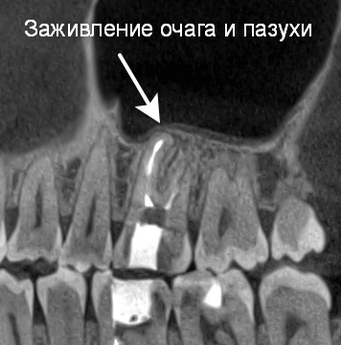

Так в следующем клиническом случае лечения апикального периодонтита мы наблюдаем очаг «воспаления» на верхушке проблемного зуба (рис. 10). Причина воспаления : инфекция в необработанных и незапломбированных каналах (рис. 11). После проведенной процедуры перелечивания системы корневых каналов (их оказалось 6, вместо ожидаемых 4!) под микроскопом мы убрали источник и воспаления и запустили иммунитет на восстановление костной ткани! На контрольных рентгенограммах мы наблюдаем полное восстановление от воспалительного процесса (рис 12).

Рис. 12 Контрольный снимок через 5 месяцев